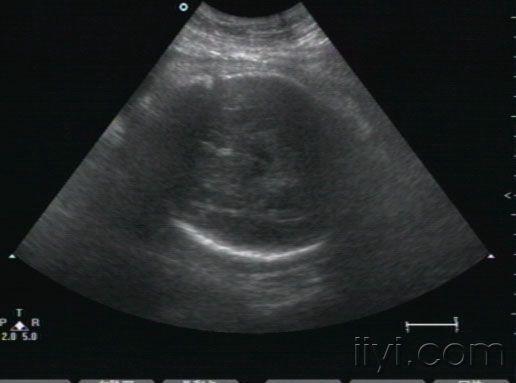

胎儿心包积液

• 孕38周,10天以前在多家医院检查胎儿正常。近一周来自觉腹胀,下坠。发现胎儿心包积液,并且右室壁好象很厚。胎儿生下来后,临床医生没有听到杂音,遗憾的是孩子也没来检查心脏。我们没有开展胎儿心脏,请各位专家帮忙看下,到底是什么原因,胎儿右室壁增厚考虑什么病,为什么生后没有杂音呢?